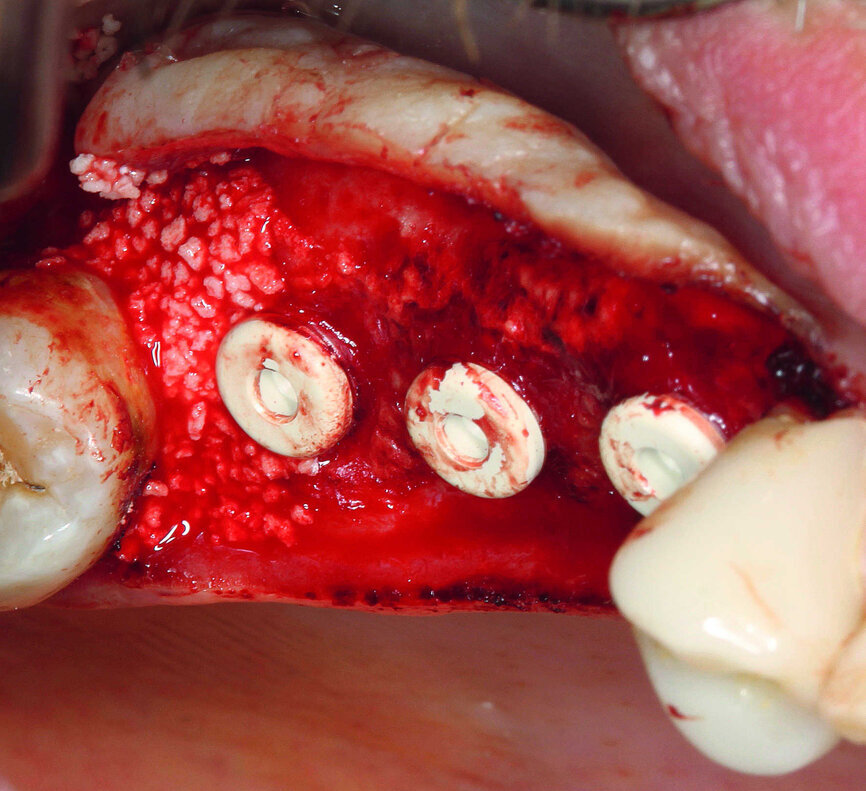

Fig. 14 : Implants insérés avec hauteur supracrestale comprise entre 0,5 mm et 1,0 mm.

Le modèle des implants utilisé pour ce cas était favorable à la faible hauteur osseuse existante et écartait de ce fait le risque d’un glissement dans le sinus maxillaire. Les implants en zircone sont fabriqués par un procédé de moulage par injection de céramique (MIC) permettant l’obtention de deux surfaces différentes. La texture de surface dans la zone du col est moins rugueuse que dans la partie endo-osseuse et favorise l’apposition du tissu mou, tandis que la surface endo-osseuse est optimisée pour l’ostéointégration. Les implants ont été insérés en laissant une hauteur supracrestale de 0,5 mm environ, et un couple de 25 Ncm a suffi pour obtenir la stabilité primaire (Fig. 14). Après l’insertion des implants, la membrane de collagène se trouvait en position apicale, tel un écran placé au-dessus des implants de la région dentaire 16–17, qui pénétraient de deux ou trois millimètres dans le plancher du sinus. Un caillot de sang s’était formé dans la cavité créée et favorisait la régénération d’un os stable, grâce à la production de facteurs de croissance durant le processus de cicatrisation des implants.7 Le défaut intra-osseux parodontal au niveau de la dent 18 a été comblé avec un phosphate tricalcique bêta pur (Fig. 15).

Mélangés avec du sang prélevé au niveau du site chirurgical du patient, les granules poreux de phosphate tricalcique bêta d’origine synthétique sont faciles à appliquer. Au bout de six à neuf mois, le matériau se régénère en os cortical stable. Après le recouvrement des implants par une coiffe de protection en polyéther éther cétone (PEEK), la plaie a été fermée sans tension au moyen de deux sutures matelassées et plusieurs sutures simples discontinues (Fig. 16). Ensuite, une radiographie a été prise pour un contrôle (Fig. 17). 8 Le patient a quitté le cabinet dentaire avec de nouvelles instructions concernant la conduite à tenir après l’intervention, insistant sur les soins et l’absence de toute pression.